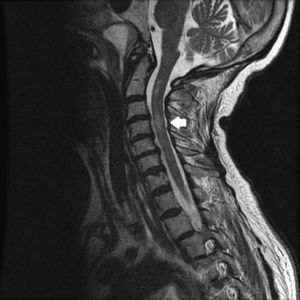

Se presenta el caso de una mujer de 71 años con antecedentes de dislipemia, fibromialgia, síndrome de piernas inquietas y poliartrosis. Acude a urgencias por cervicalgia súbita, punzante, sin antecedente traumático, asociada a parestesias y debilidad de miembros superiores (balance motor: deltoides 3/5 bilateralmente, resto 4/5 globalmente). La radiografía cervicodorsal resultó normal procediendo al alta con analgesia. Cinco horas después consulta nuevamente por progresión de la clínica, mostrando debilidad en extremidades e incontinencia de esfínteres, sin signos inflamatorios ni infecciosos. A su llegada al hospital presenta un índice de Glasgow 15 con buen estado general, sin embargo, durante el procedimiento de monitorización se aprecia una disminución del nivel de conciencia (índice de Glasgow 3), en el contexto de insuficiencia respiratoria severa con marcada hipercapnia (pCO2 102mmHg), procediendo a intubación orotraqueal, ventilación mecánica e ingreso en la unidad de cuidados intensivos (UCI). Se realizó TAC cerebral urgente que no mostró alteraciones. En la resonancia magnética (RM) medular efectuada 2 días después, se aprecian cambios hiperintensos en secuencias potenciadas en T2 en la médula cervical en su vertiente anterior y central desde C2 hasta C5, compatibles con isquemia (fig. 1). La analítica sanguínea incluyendo hemograma, perfil renal y hepático, proteinograma, hormonas tiroideas, vitamina B12, ácido fólico, estudio de coagulación y autoinmunidad, pruebas reumáticas, serología para sífilis, brucella y virus neurotropos resultó normal, descartando causa infecciosa, carencial, hematológica o autoinmune. Se solicitó ecografía transtorácica y estudio angio-TAC de arterias cerebrales, resultando ambos normales. El análisis de líquido cefalorraquídeo (citobioquímica, cultivo y PCR de herpes virus) tras punción lumbar no mostró alteraciones. Al tercer día se apreció movilidad en miembros inferiores, con balance motor 2/5 globalmente; previamente presentaba tetraplejía con puntuación motora (PM) 0/100 en la escala de American Spinal Injury Association (ASIA), persistiendo cuadro de distress respiratorio, que requirió traqueostomía reglada.

En la RM se aprecia en secuencias potenciadas en T2 lesiones hiperintensas lineales en cortes sagitales, como dibujadas como un lápiz «pencil-like», a veces con ensanchamiento medular, y generalmente bilaterales; y en cortes axiales se observa alteración de señal en las astas anteriores de la sustancia gris medular, que produce una imagen en «ojos de búho»8. No existe evidencia en la efectividad del tratamiento, aunque se han empleado corticoides, antiagregantes o la oxigenación hiperbárica. Otras medidas como el drenaje lumbar para mantener la presión de LCR<10cmH2O y el control de la presión arterial media >90mmHg han mostrado mejoría en algunas series9.